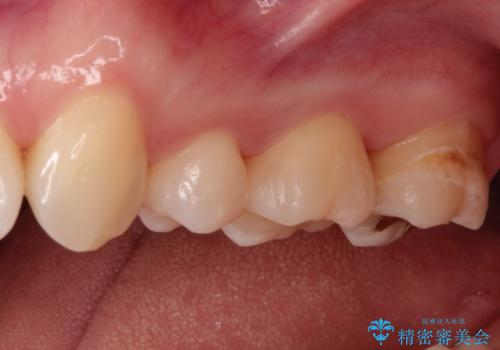

- 他院で虫歯になっていると指摘され来院されました。適合の良いゴールドインレーによる治療がされていましたが、違う部分が虫歯になってしまっていました。審美性の良いセラミックインレーを希望されました。

ゴールドインレーを除去し、その下で広がっていた虫歯をきれいに取り除きました。

一度治療した歯も再び虫歯になる可能性があるので、定期的なチェックが大切になります。